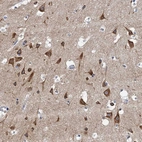

Immunohistochemistry analysis in human cerebral cortex and liver tissues using HPA039730 antibody. Corresponding NBEA RNA-seq data are presented for the same tissues.